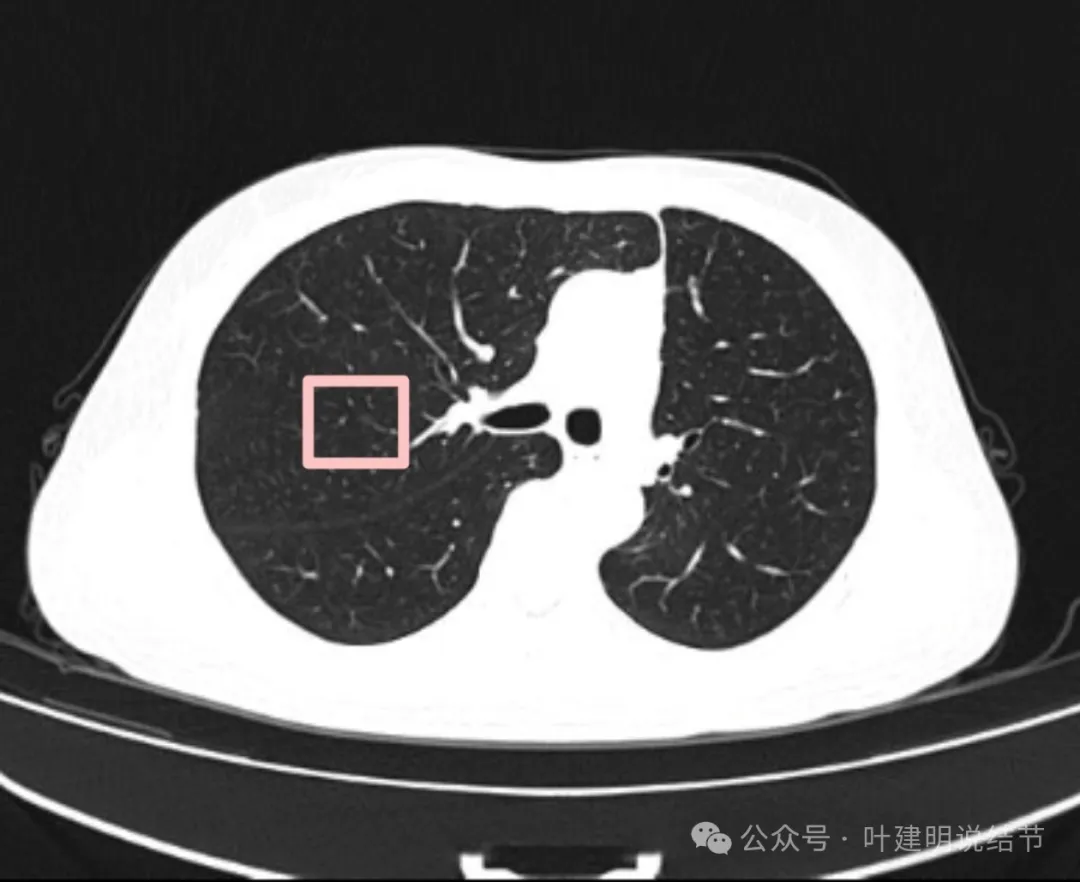

影像展示与分析:

左下叶主病灶实性,收缩力较弱,胸膜略有牵拉,表面似乎较为光滑,毛刺不明显,血管征不明显,整体密度显得较高。

局部放大了看,边缘略毛糙;胸膜略牵拉;灶内有小区域密度偏低的空泡或偏低密度区;表面似有较为勉强的分叶征的样子。但整体说不上明显收缩力,磨玻璃成分也不大明显。

我看有所异常的就是这几处(次要病灶未展示)。桔色圈起来的过小过淡的磨玻璃结节,考虑肺泡上皮增生可能性大,感觉没到不典型增生,先年度随访;黄色圈起来的微小实性,考虑良性的;蓝色的这处密度高,似乎良性的可能性大,但一是随访有增大,二是有胸膜牵拉,三是位置好,而若真恶性,实性风险大。我个人倾向4-6个月后左下叶靶扫描下,如果有恶性可能,则还是手术切了化验比较放心。意见供参考!